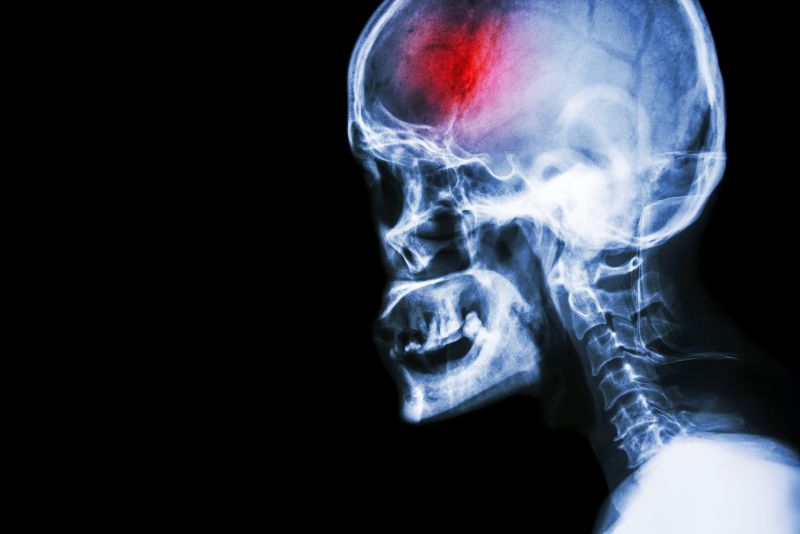

A stroke (previously known as a cerebrovascular accident) when there is a decreased flow of blood to the brain from either a blockage in the blood vessels that supply the brain (ischemic stroke), or a bleed from the blood vessels that supply the brain (hemorrhagic stroke). When the blood flow to the brain is blocked it prevents the brain from getting the needed oxygen and nutrients to function. Without oxygen the brain cells can be permanently damaged or die and the physical and mental functions related to that area of the brain will be affected. A stroke is a medical emergency and rapid treatment is crucial to decreasing the damage caused by a stroke.

- Ischemic stroke: a stroke that is caused by a blockage (clot) that disturbs the blood flow to the brain.

- Hemorrhagic stroke: a stroke that is caused by a bleed that disturbs the blood flow to the brain and puts pressure on the surrounding tissue.

- Transient ischemic attack: often referred to as a “mini-stroke” or TIA, where the blood flow to the brain is temporarily disturbed and as a result causes temporary signs and symptoms of a stroke that resolve quickly .